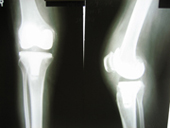

Arthriis of both hips pre op Arthriis of both hips post op Arthritis knee valgus deformity pre op Arthritis knee valgus deformity post op

Arthritis both knees varus deformity pre op Post op Total Knee Replacement Post op Total Knee Replacement